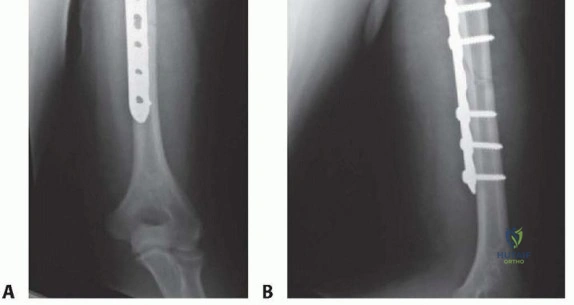

Clinical & Radiographic Imaging